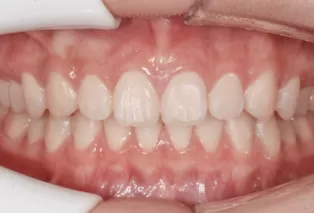

Photos intra-orales après traitement